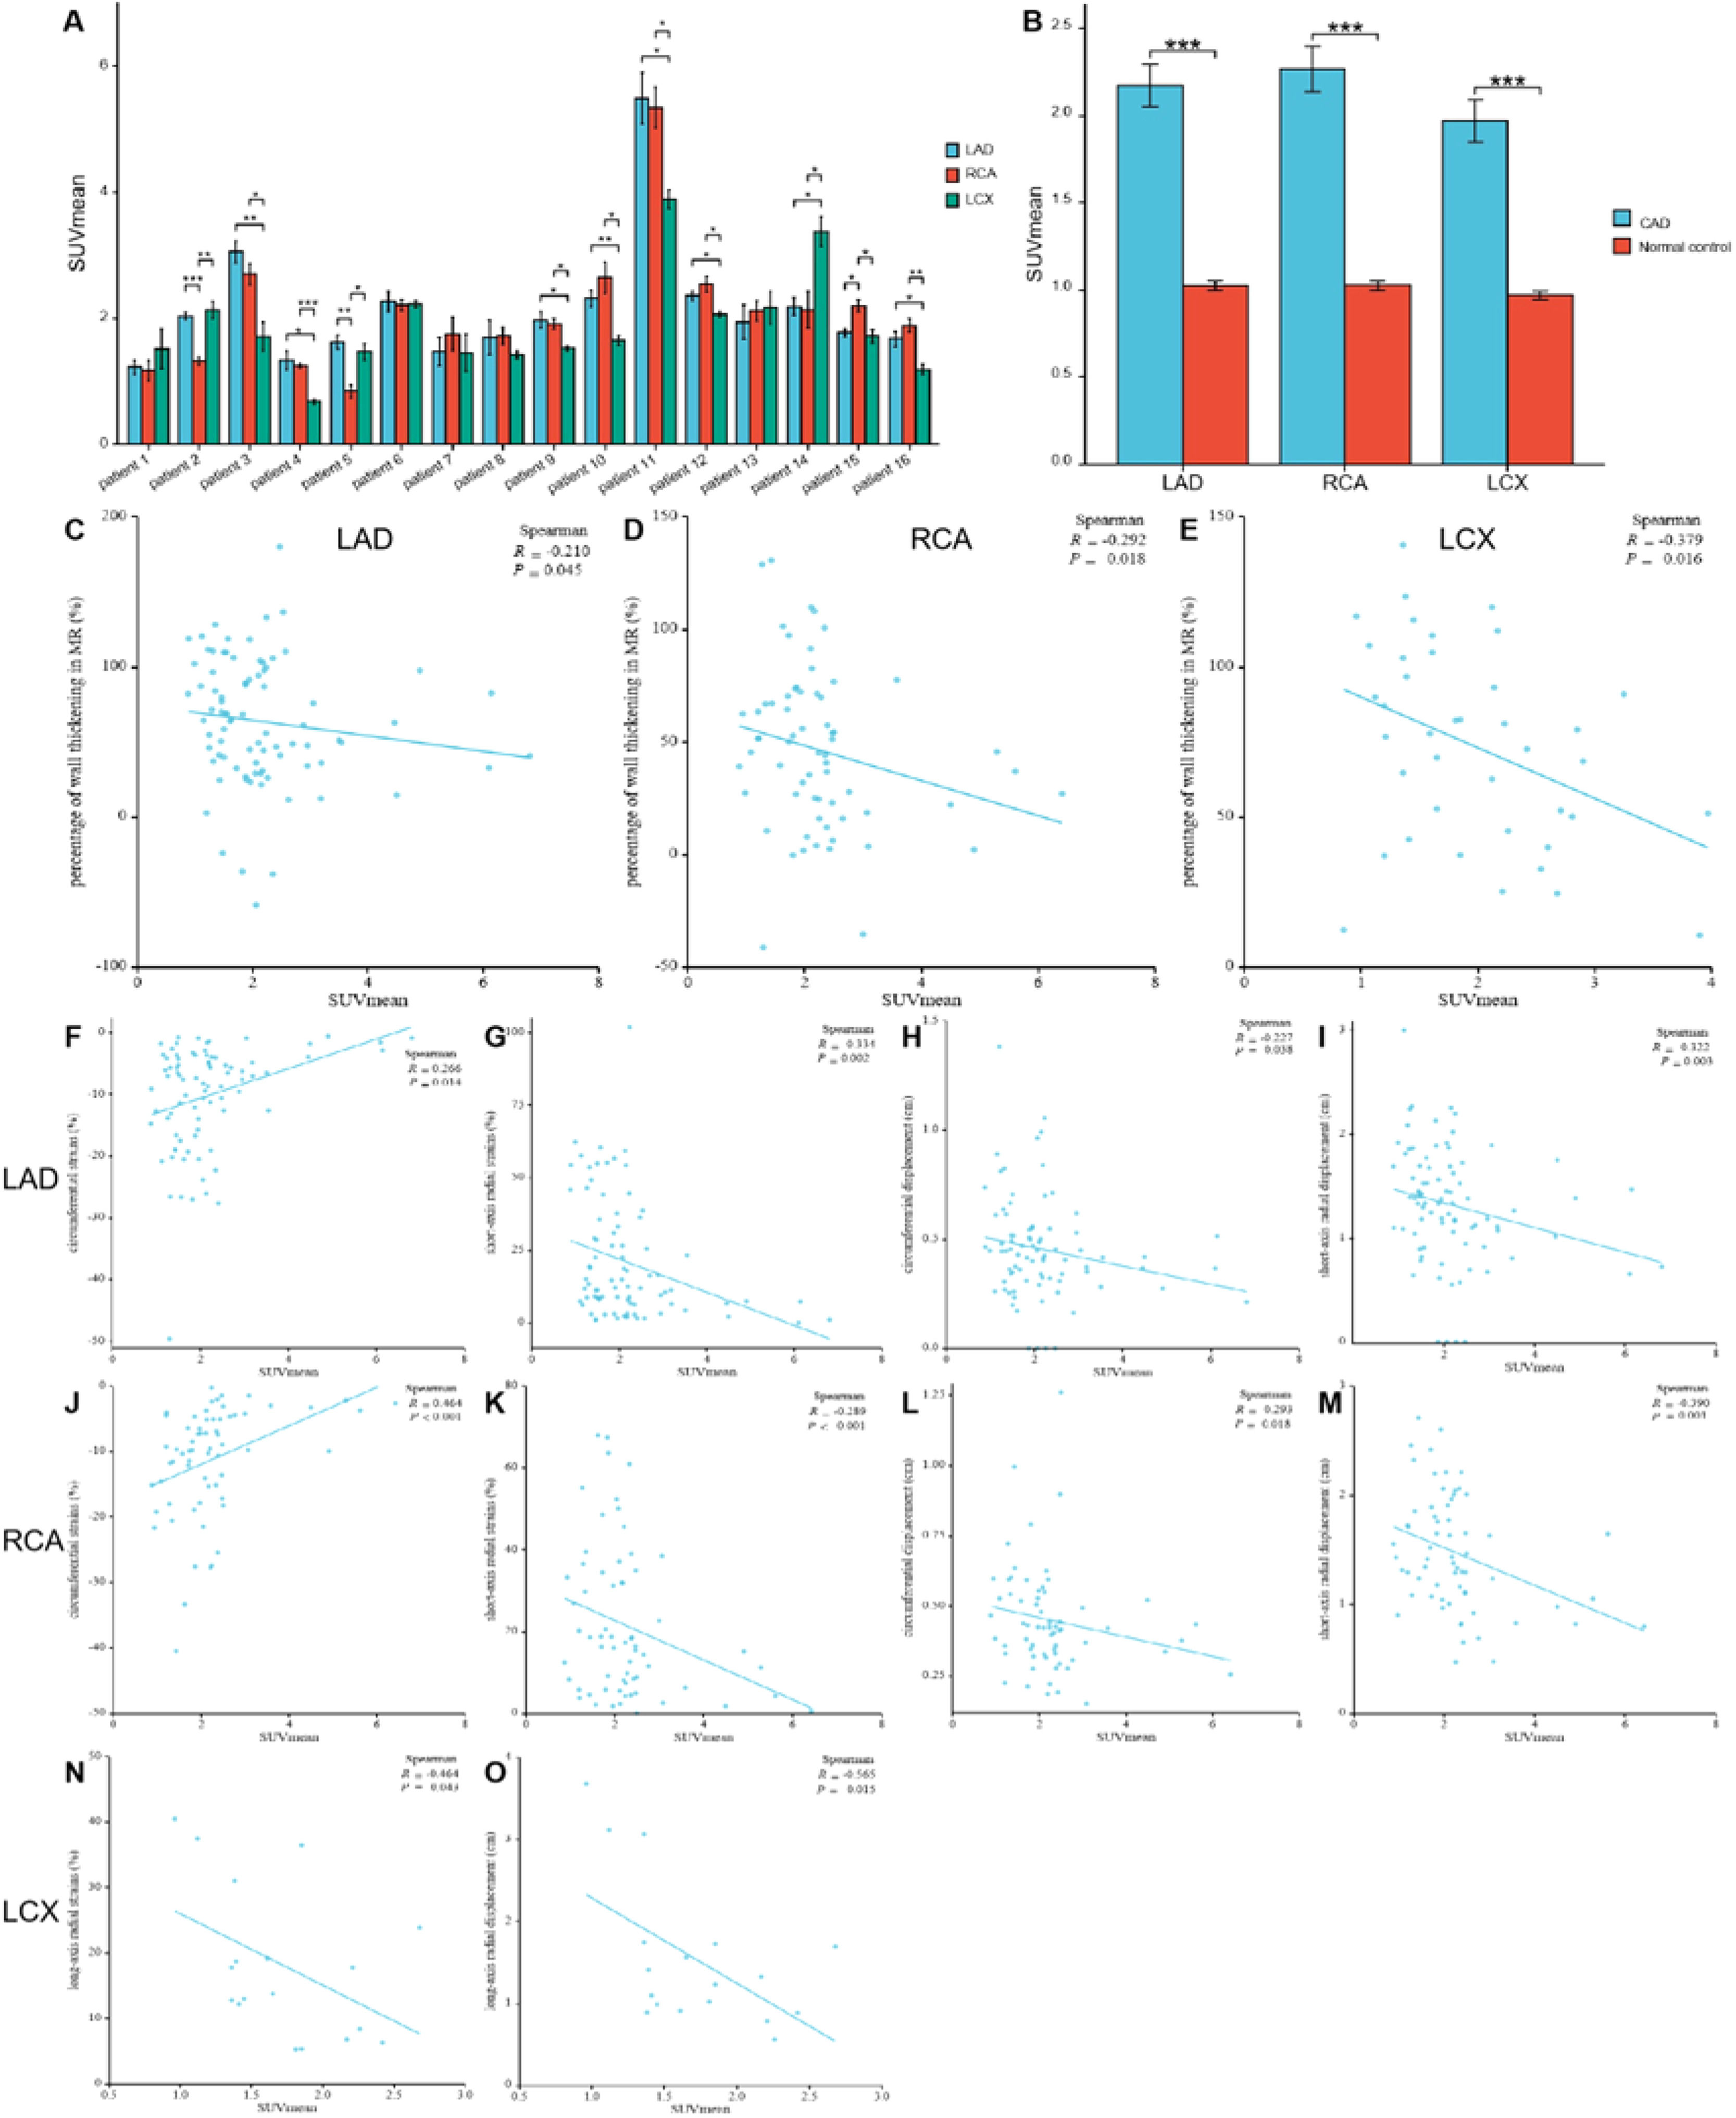

The comparison of SUVmean in the myocardium fed by every coronary artery in each participant with Coronary Artery Disease (CAD) (A) For each participant, FAPI uptake was significantly higher in the myocardium fed by the narrow coronary artery than that fed by normal coronary artery. The comparison of SUVmean between in the myocardium fed by the coronary artery with stenosis in CAD participants and in those fed by the corresponding normal coronary artery in normal ones (B). It showed that uptake of FAPI in the myocardium fed by every coronary artery with stenosis was significantly higher than that in the same myocardium fed by non-occluded coronary artery. The correlation analysis between percentage of wall thickening and SUVmean in the myocardium fed by anterior descending coronary artery (LAD), Right Coronary Artery (RCA) and Left Circumflex Artery (LCX), respectively (C‒E). The correlation analysis between the peak circumferential and short-axis radial strains and displacements and SUVmean in LAD and RCA, respectively (F‒M). The correlation analysis between the long-axis radial strains and displacements and SUVmean in LCX (N‒O). Each column represents mean ± SD. Asterisks indicate significant differences between them. * p < 0.05, ** p < 0.01, *** p < 0.001.

Comparison between CAD patients and healthy controls revealed significantly higher FAPI uptake in ischemic myocardial regions supplied by stenotic coronary arteries than those fed by non-occluded vessels. The SUVmean from the myocardium fed by the same coronary artery in the CAD and healthy controls were as follows: LAD: 2.16 ± 1.12 vs. 1.02 ± 0.21; RCA: 2.27 ± 1.06 vs. 1.03 ± 0.19; LCX: 1.97 ± 0.76 vs. 0.97 ± 0.18 (all p < 0.01; Fig. 4B).

Analysis of corresponding abnormal blood-supplying myocardial areas delineated by the three major coronary artery branches in the polar maps from the short-axis view of the CMR images revealed inverse correlations between the percentage of systolic LV wall thickening and FAPI uptake (SUVmean) (LAD, r = -0.210, p = 0.045; RCA, r = -0.292, p = 0.018; LCX, r = -0.379, p = 0.016) (Fig. 4C‒E). Moreover, the peak circumferential and short-axis radial strains and displacement of the corresponding orientation in the LAD- and RCA-supplied myocardial areas were inversely correlated with FAPI uptake (SUVmean). The results were as follows: peak circumferential and short-axis radial strains for LAD, r = 0.266, p = 0.014 and r = -0.334, p = 0.002; for RCA, r = 0.464, p < 0.001 and r = -0.289, p < 0.001, respectively; and circumferential and short-axis radial displacements for LAD, r = -0.227, p = 0.038 and r = -0.322, p = 0.003; for RCA, r = -0.293, p = 0.018 and r = -0.390, p = 0.001 (Fig. 4F‒M). In addition, the peak long-axis radial strain and displacement in the LCX-supplied myocardial areas were inversely correlated with FAPI uptake (SUVmean). The results were as follows: r = -0.464, p = 0.043 and r = -0.565, p = 0.015, respectively (Fig. 4N‒O).